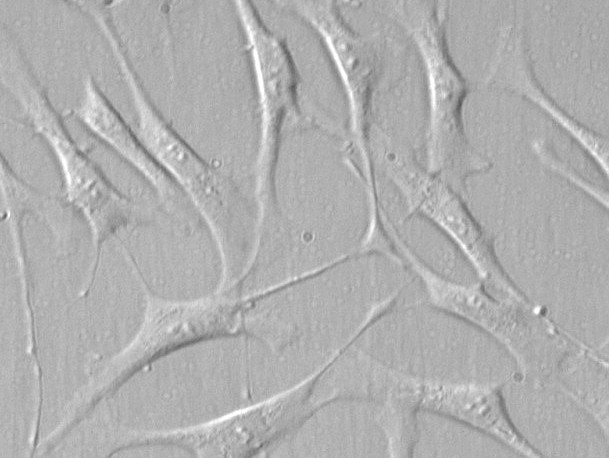

来自ScienCell研究实验室的HTMC分离自人眼的近关节和角膜巩膜区域。HTMC在P0冷冻保存并冷冻。每个小瓶含有>5×10^5个细胞,1ml体积。HTMC的特征在于具有对α-平滑肌肌动蛋白和纤连蛋白特异性的抗体的免疫荧光。HTMC对HIV-1,HBV,HCV,支原体,细菌,酵母和真菌均为阴性。在ScienCell研究实验室的条件下,HTMC保证进一步扩大15次人口倍增。

小梁网位于虹膜根部周围,并有一条通向施莱姆管的狭缝,可将水管排入静脉血管。小梁网细胞(TMC)在房水流出中起积极作用,并且该途径是眼内压依赖性的。因此,TMC的损伤或死亡与开角型青光眼的发病机制有关[1]。TMC进一步表达神经递质和神经肽的受体,并对极低浓度的各种血管活性肽和生长因子作出反应,使这些细胞能够在多个水平上调节小梁网的通透性[2]。TMC培养为研究小梁网的功能控制提供了宝贵的工具,鼓励开发更有效的治疗青光眼的策略。